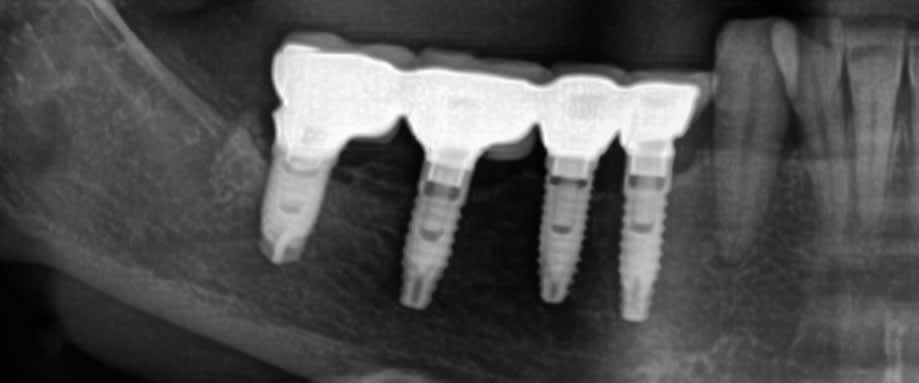

La pano.

pas évident, Pluton à peut être une idée niveau instrument, sinon taille de l'ensemble (bonjour le boulot) empreinte et prothèse sur les moignons....